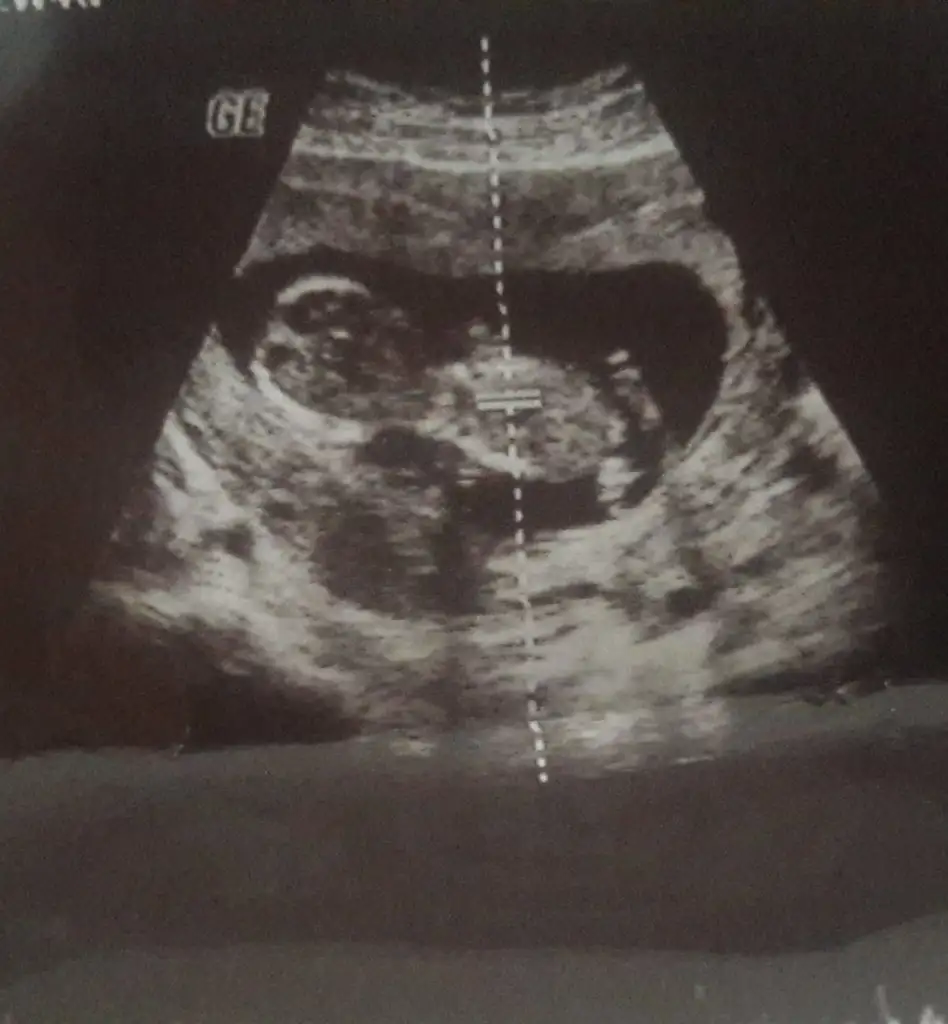

Net degil usg eminde değilim sanki kız varda başka usg paylaşın emin değilim

Kız bence 9+6 hafta ya göre

Buda kız gibi boş görünüyor bacak arasıdün gittik 14 hafta usg verdi ama belli olmuyor Eki Görüntüle 2575104